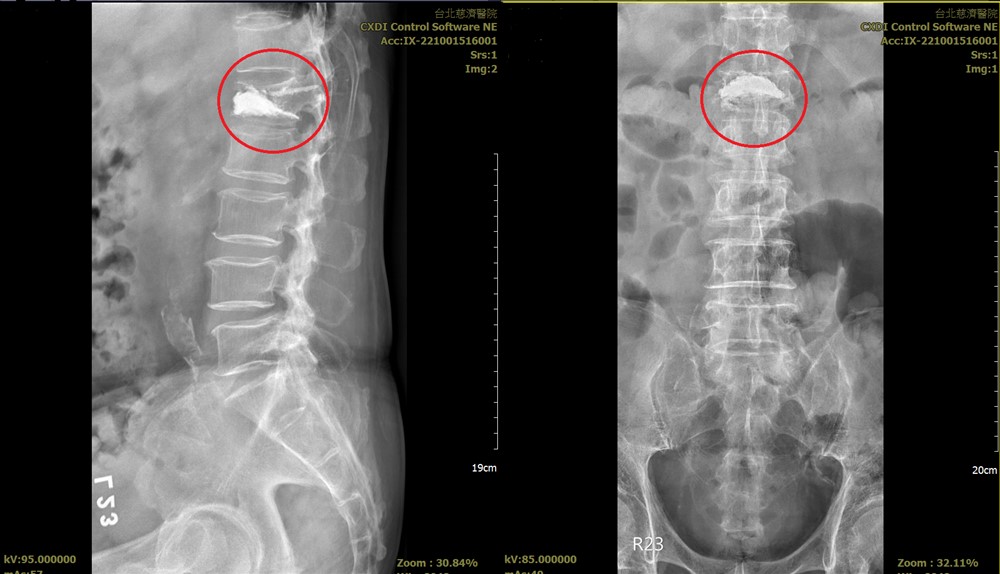

壓迫性骨折若選擇保守治療,可給予消炎止痛、肌肉鬆弛等藥物,另外搭配護腰,讓壓迫碎裂的骨頭慢慢癒合,久而久之疼痛感就會慢慢減緩,但通常需忍耐一個月的時間,得評估患者疼痛耐受度與動力受限的狀況。而針對嚴重壓迫性骨折患者,則可選擇進行微創骨水泥手術,透過三釐米的骨穿細針,在X 光影像導引下將骨水泥注入椎體骨折處,除了可大大改善疼痛,術後可大幅增強椎體強度及脊椎穩定性。

術後X 光顯示,水泥注入椎體骨折處,增強椎體強度及脊椎穩定性。圖/台北慈院提供